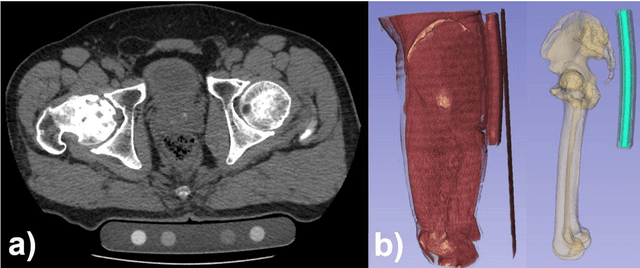

Abstract:Deep learning-based image segmentation has allowed for the fully automated, accurate, and rapid analysis of musculoskeletal (MSK) structures from medical images. However, current approaches were either applied only to 2D cross-sectional images, addressed few structures, or were validated on small datasets, which limit the application in large-scale databases. This study aimed to validate an improved deep learning model for volumetric MSK segmentation of the hip and thigh with uncertainty estimation from clinical computed tomography (CT) images. Databases of CT images from multiple manufacturers/scanners, disease status, and patient positioning were used. The segmentation accuracy, and accuracy in estimating the structures volume and density, i.e., mean HU, were evaluated. An approach for segmentation failure detection based on predictive uncertainty was also investigated. The model has shown an overall improvement with respect to all segmentation accuracy and structure volume/density evaluation metrics. The predictive uncertainty yielded large areas under the receiver operating characteristic (AUROC) curves (AUROCs>=.95) in detecting inaccurate and failed segmentations. The high segmentation and muscle volume/density estimation accuracy, along with the high accuracy in failure detection based on the predictive uncertainty, exhibited the model's reliability for analyzing individual MSK structures in large-scale CT databases.